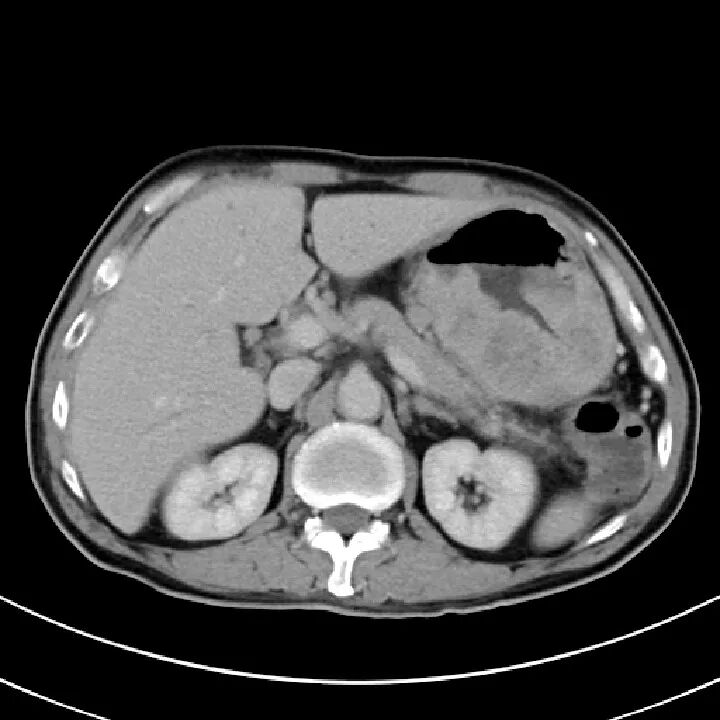

胰腺损伤

在交通意外中,尤其是汽车驾驶人员当汽车高速行驶中,汽车骤然撞于物体上,其强大的惯性使驾驶者的上腹部撞击于汽车方向盘上,导致胰腺受伤。有时当人体自高处坠落,腰部呈过度层曲,同时双侧肋弓极度内收,瞬间一个暴发力,挤压于胰腺上,造成胰腺不同程度的损伤。

胰腺损伤的部位,随外力的方向而异,以胰腺头、体部常见。当外力作用于右上腹或脊柱右侧方,则胰头部易被挤压,同时常合并有十二指肠、胆道、肝脏损伤,此类损伤后果严重,死亡率甚高可达70%~80%;当外力直接作用于上腹中部,则损伤多为胰颈、体部的部分或完全断裂,并合并有肠系膜上动脉损伤;外力作用于脊柱左侧方,胰尾常易受伤,此时多伴有脾破裂。